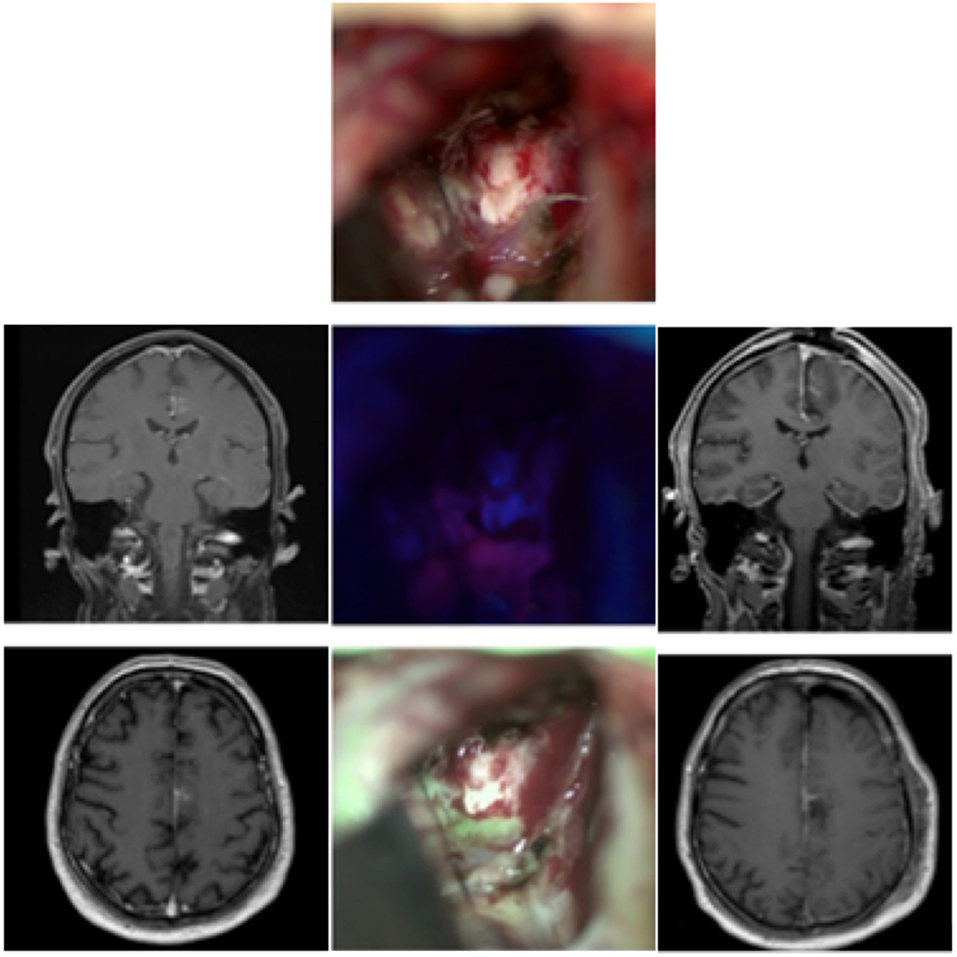

FIGURE 1

www.frontiersin.org

Figure 1. Glioblastoma in a 53-year-old patient. The left column shows the MRI images (T1 weighted with contrast, from top to bottom: coronary, axial, sagittal) before the operation, the right column the postoperative MRI. In the middle column, the top picture shows the surgical field under white light, below it under blue light, and at the bottom the fusion of both images in the MFL-mode.

Case 1: Glioblastoma (Figure 1)

A 53-year-old male reported to our clinic with persisting headaches, amnesia, concentration deficits, confusion, and coordination deficits on the left side. This was accompanied by a tendency to fall to the left and insecure gait. The initial CT scan obtained showed a lesion in the right temporal-parietal region with significant surrounding edema. The cranial MRI scan revealed a lesion highly suspicious for GBM. We, therefore, scheduled the patient for the resection of the lesion. Prior to the intervention the patient received 20 mg per kilogram bodyweight of 5-ALA. Microsurgical resection of the tumor was performed with the modified microscope and concurring sonographic navigation and neuronavigation. The use of the MFL mode showed a coherent fusion of both white light and blue light images of the highly fluorescent tumor tissue and allowed for easy assessment of any bleedings occurring throughout resection. A tissue sample of the resected tumor was sent to the affiliated department of neuropathology and revealed a GBM. After the operation at the final neurological examination the patient presented himself with no neurological deficits and was totally mobile. Postoperative MRI showed a complete resection of the tumor.